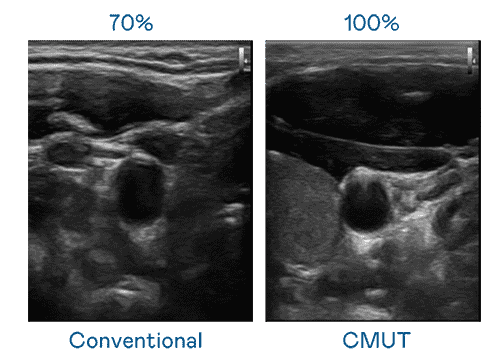

CMUT 技术是一种用电容式微机电元件来产生超音波讯号的技术。。与传统 PZT 压电式技术相比,,,CMUT 频宽增加 30%,,更宽频的超音波讯号让影像解析度大幅提升,,,是实现高影像品质医疗超音波扫描、、、、促进精准医疗发展的关键技术。。。

大频宽带来超清晰影像

超音波影像的解析度高低,,,首先取决于探头能发出的讯号频宽。。。z6mg·人生就是博 CMUT 可提供高清晰的超音波讯号,,提供高频宽、、、、高灵敏度、、影像纹理细节更高的超音波影像,,,协助医护人员缩短影像判读时间及利用精准的医疗影像进行诊断。。。。